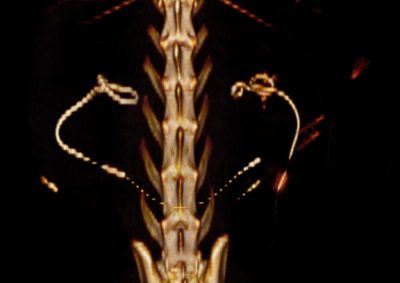

猫の尿管結石に対するSUBシステム(人工尿管設置)